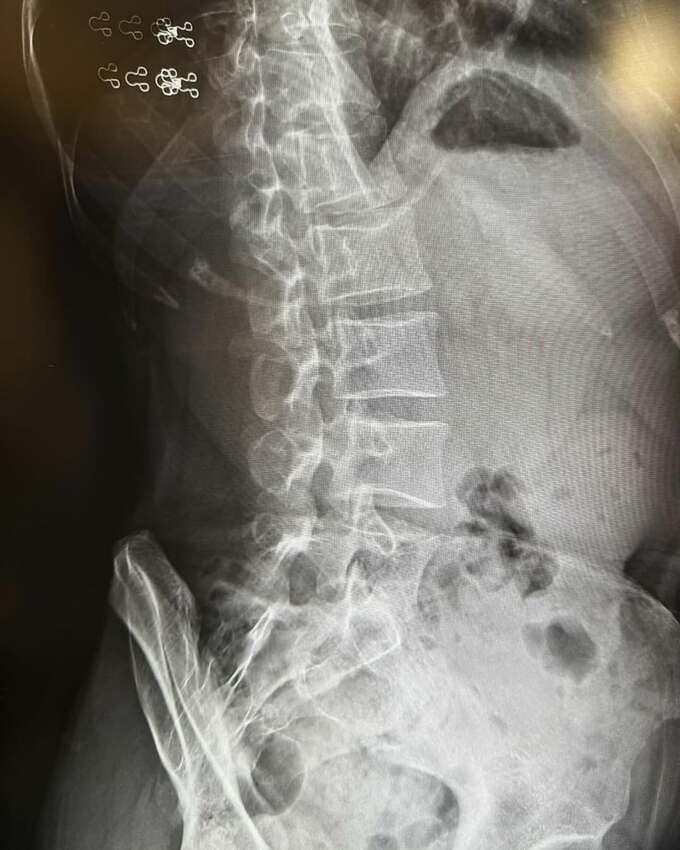

新井さんは、腰のレントゲン写真を添えて、「はじめて、所謂ぎっくり腰になりました」と投稿。その発症の瞬間について、「ソファに座る長男に『どれにする?』と絵本を差し出した瞬間、ピキ!っときまして、『これか』と思いましたね 動けなくなる感じ…。」と振り返りました。

2日間自宅で安静にした後、病院へ行ってレントゲンを撮り、「理学療法を施してもらい、薬による痛み止めで治るのを待つことになりました」ということです。